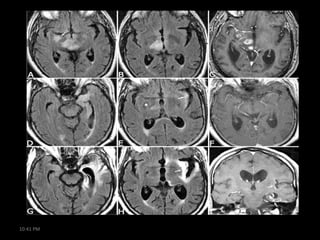

Encephalomyelitis

• Cancer patients with clinical signs of damage to

more than one area of the nervous system

• Limbic encephalitis

•

rare complication of small-cell lung cancer

personality/mood changes develop over days or weeks

severe impairment of recent memory

sometimes with agitation, confusion, hallucinations, &

seizures

• brain MRI: normal or signal changes in the medial temporal

lobe(s)

• may improve with treatment of underlying tumor